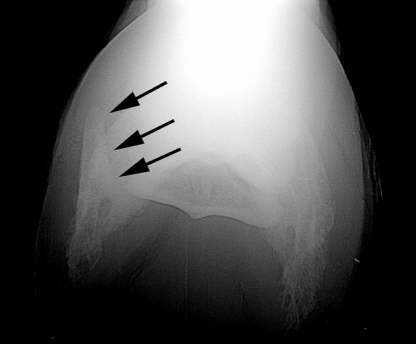

Skyline Aufnahme

Hufknorpelverknöcherung